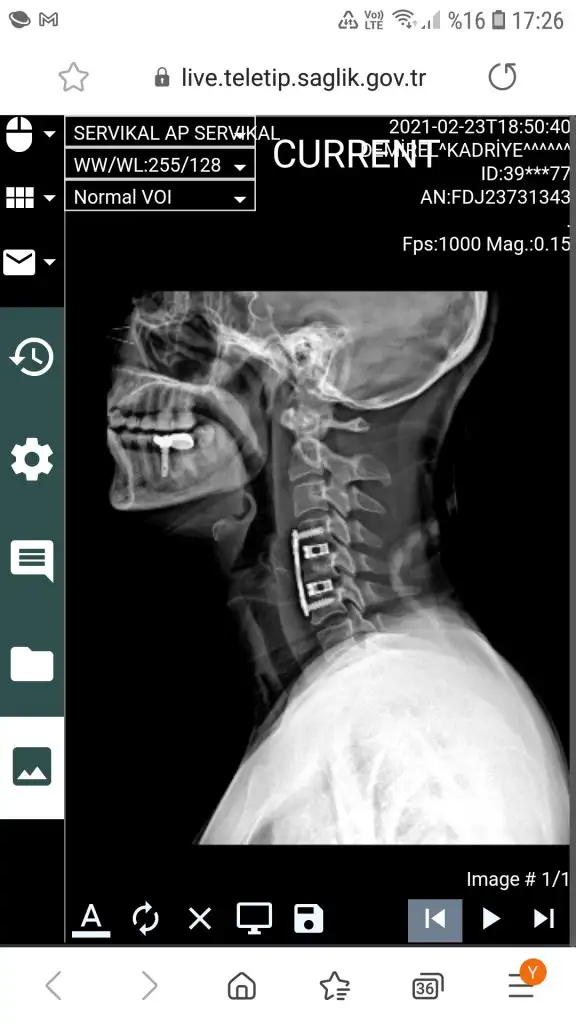

kızlar merhaba ben 20 gün önce oldum boyun fıtığı ameliyatını canım takılan protezin kayma şansı yok o kaynayana kadar asıl olay ameliyat olmaya kara verdiğinde başlıyor. Benim 4 tane fıtığım var 1 tanesi 5 senedir omuriliğime basıyordu ama benim pek şikayetim yoktu, gece seneden bu yana sonuçlarım zaten ameliyattı, ameliyattan başkada yapılacak bişey yoktu. Benim sonuçlarıma bakan doktorlar inanamıyordu hatta gecen sene senin ya sedyede yada ölüyorum diye gelmen gerek bu sonuçlarla dedi doktorum.

Bana ameliyattan başka yapılacak birşey olmadığını her doktor söyledi aklına gelen bütün hastanelere gittim. Açık konuşmak gerekirse felç başlayınca olurum dedim doktorlarda onaylamıştı çünkü şikayetim yoktu. Bu sene omuriliğimde zedelenme başlamıştı sağ tarafımda sinir zedelenmelerinden felçte başlamış ama ben farketmedim bile sadece senelik kontrole gitmiştim. Ameliyatımı oldum hiç bir şikayetim yok boyunluk takmak haricinde çünkü tahriş oldu boynum malesef. 2 ayrı yöntem var ameliyat olmak istediğin zaman önemli olan hangisine karar vereceğin. Biri disk protez diğeri füzyon.

Canım fıtıklarımız aynı c5-c6dan ameliyat oldum. C2-C3 tede var o ufak benim diğer 2 fıtığım başka yerlerde bendede toplam 4 tane var yani 3 kaldı.

2 ayrı yöntem var biri disk protez diğeride kemik tozu dediğin füzyon. Canım şöyle anlatayım ben yönteme karar vermek için 20 gün dolandım kemik tozu dediklerini bi protez var o takılıyor onun içinde boşluk var kemik tozu veya benzeri şeylerle kemiklerin birbirine kaynaması sağlanıyor, gerçek kemik bu protezler bulunmadan önce kalçadan alınıp takılıyormuş artık yapan yok gerekte yok zaten. Bu yöntemle %7 hareket kısıtlaman oluyor kafanı sağa sola yukarı aşağıya %7 çeviremiyorsun. Doktorlar farketmezsin çok fazla diyor aynı protezden 2 yada 3 tane takılcakki o zaman farkedersin zaten o zamanda kafayı pek oynatamazsın zaten. Diğer yöntem harika disk protez hiç bir hareket kısıtlaması yok boyunluk bile takmak zorunda kalmıyorsun ameliyattan sonra ama 8-10 yıldır kullanılan bir yöntem bu ve gelecekte ne olacağı bilinmiyor. Yorulma ömrü 15-20 yılmış yani 15-20 yıl sonra %90 değiştirilmesi gerekecek belki içinde kırılacak allah korusun genç olduğumuz için bazısı kesin bu yöntem diyor bazısı asıl gençsin diye kesinlikle olmaz diyor. Canım ben ve eşim makina mühendisiyiz oturup doktorlarlada herşeyini inceledik boynumuza yüklenecek yük parçanın yorulma ömrüydü şuydu buydu mekanik kısımları biz füzyona karar verdik en azından ömürlük çözüm bi daha aynı yerde sıkıntı olmayacak sadece biraz hareket kısıtlılığı olacak. Disk protezde birde şu var kemik deforme oluyor, 2. ameliyat çok daha fazla riskli ve aynı yöntemi bi dahada kullanamazsın bence 2 omuruna zarar vermiş olcaksın çıkarttıklarında.

Merheba ben 39 yaşındayım benimde iki fıtığım var c5 ve c6 sol tarafta sağ tarafımda da kireçlenme oluşmuş oldukça büyük fıtıklarımın olduğu söylendi ameliyat dendi benim şikayetim kollarımda çabuk yorulma boynumda ağrı el parmaklarımda ağrı, güç kaybım yoktu ameliyatı kabul ettim onayladım 10 gün oldu ameliyat olalı ,ben hızlı toparlandım ameliyat sonrası en çok yutkunurken olan boğazda ağrı beni çok zorladı tükürüğümü bile çok zor yuttum yutkunma hissi gelicek diye ödüm kopuyordu ama neyseki 4 gün sürdü bu zorlanma şimdi çok şükür iyiyim ben hemen ayağa kalktım dışarı çıktım bakkala markete parka her yere gittim birazda tez canlıyım bide benim acı eşiğim yüksek fazla ay ay ay oy oy oy yapmadım makinaya çamaşır attım astım vs kısacası bir kaç gün içinde toparlandım 2 gün dür ağrı kesici içmiyorum ve sadece ağrı kesici olarak parol kullandım ameliyatım 3 buçuk saat sürdü hastanede 2 gün kaldım 2 pilak takıldı sağ tarafımdaki kireçlenmede kazındı artık hiç fıtığım kalmadı şimdilik iyi gidiyo sonrasını zamanla görücem bide ben boyunluğumu yatarkende hiç çıkartmadım ameliyat boynumun sağ ön taraftan yapıldı gece yatarken yüksek yastık ve sol yan tarafıma rahat yattım korkulacak bişey yok artık tıp çok ilerledi ne kadar çok sorup araştırırsanız okadar çok kafanız karışır şimdilik yaşadıklarım bukadar merak ettikleriniz olursa cvp larım.